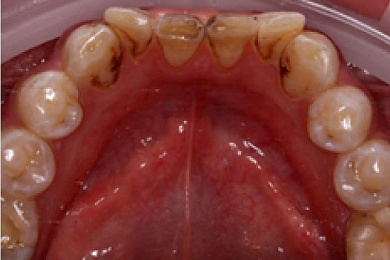

Результат лечения